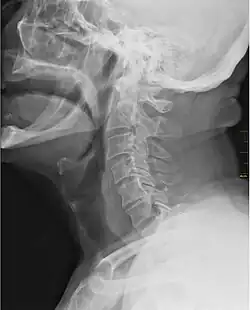

X-ray showing the throat, seen as a dark band to the front of the spine

In vertebrate anatomy, the throat is the front part of the neck, internally positioned in front of the vertebrae. It contains the pharynx and larynx. An important section of it is the epiglottis, separating the esophagus from the trachea (windpipe), preventing food and drinks being inhaled into the lungs. The throat contains various blood vessels, pharyngeal muscles, the nasopharyngeal tonsil, the tonsils, the palatine uvula, the trachea, the esophagus, and the vocal cords.[1][2] The throat is supported by structures such as the hyoid bone and cartilage of the larynx.